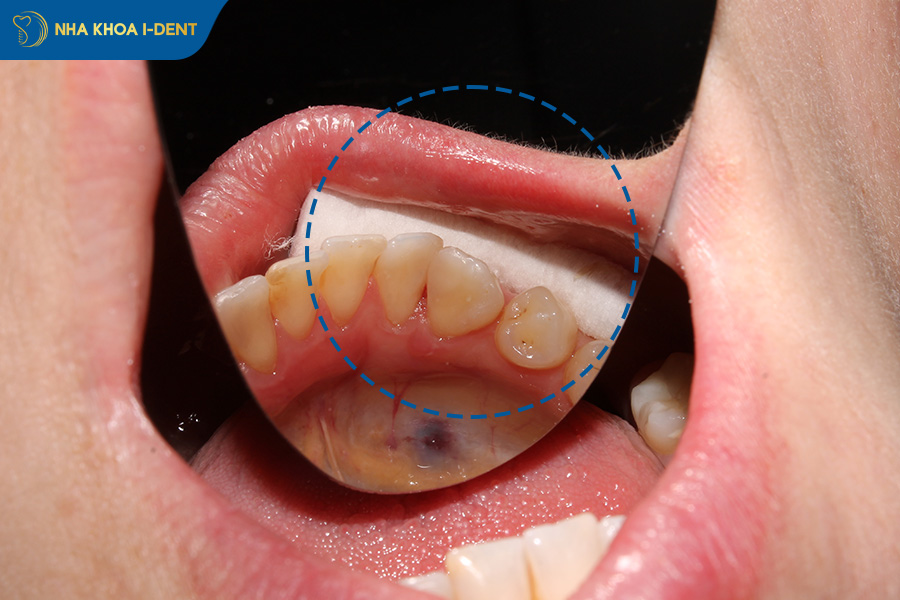

- Sưng nướu và má: Vi khuẩn tấn công gây viêm, khiến vùng má bị sưng to và khó khăn khi há miệng.

- Nhiễm trùng lan rộng: Vi khuẩn không được làm sạch sẽ lây sang các răng bên cạnh, gây viêm lợi hoặc thậm chí là nhiễm trùng máu rất nguy hiểm.